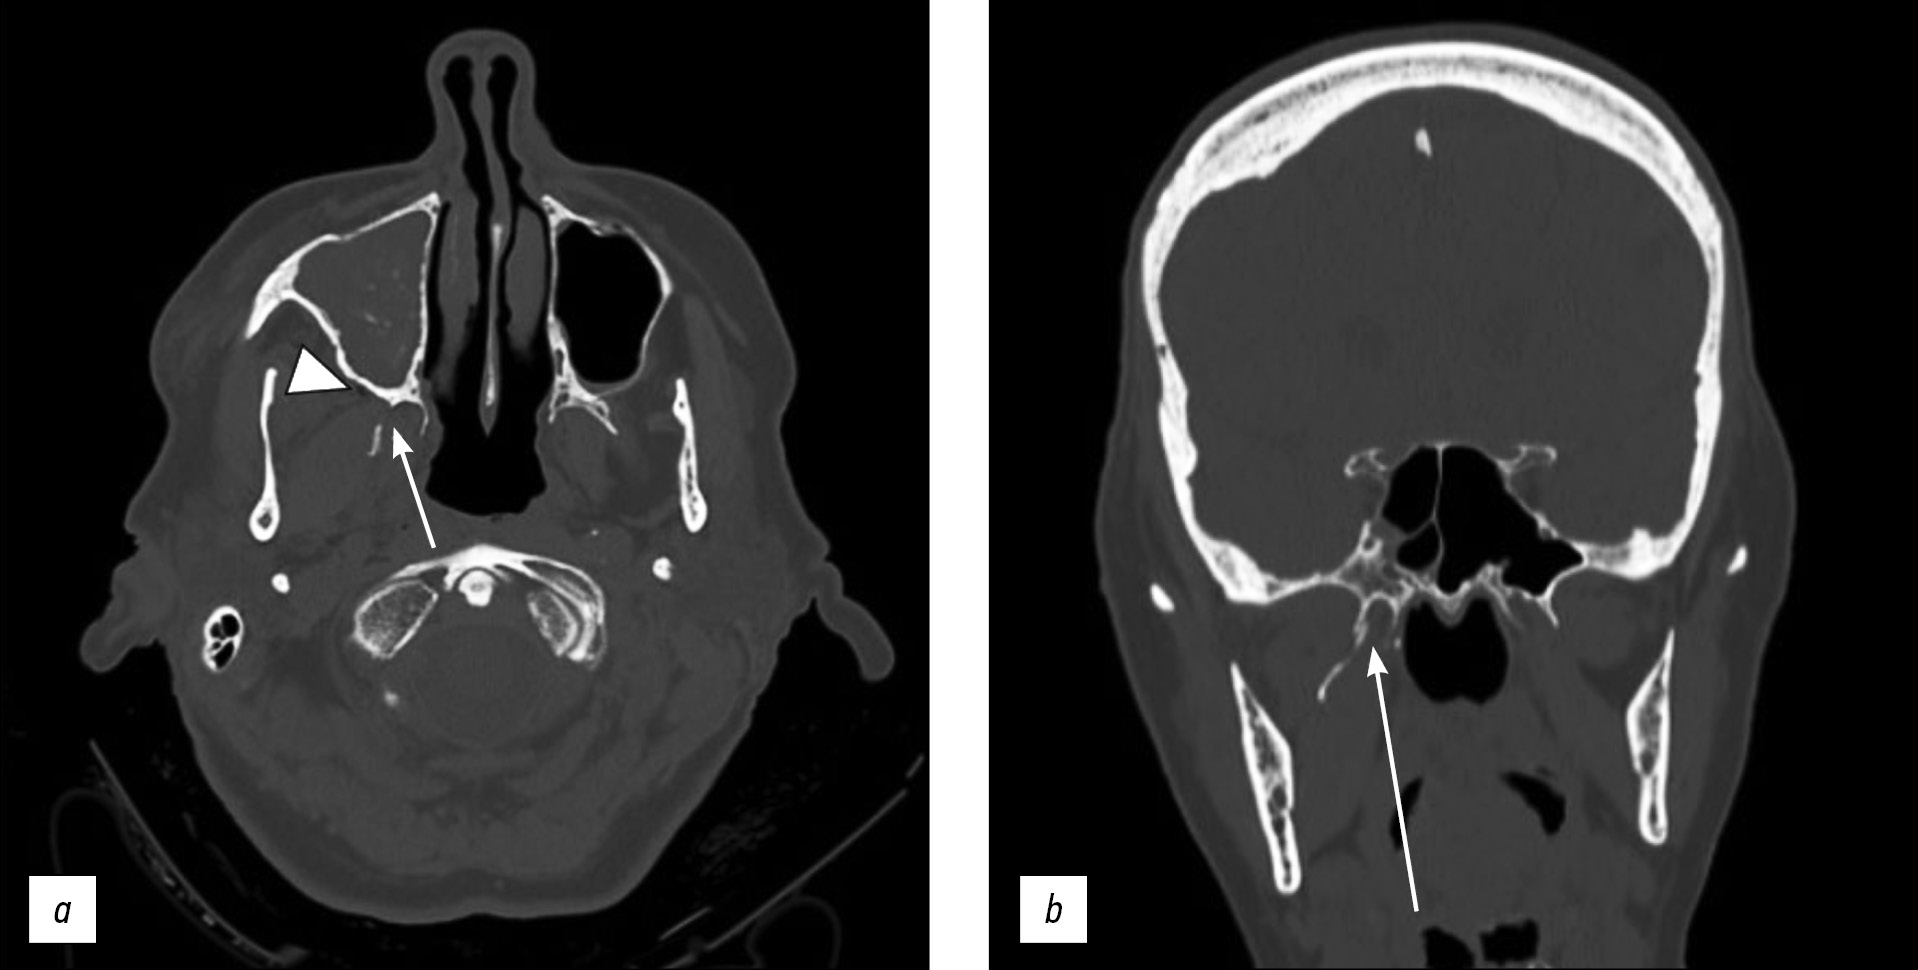

Unilateral isolated fracture of the pterygoid plate: a case report

Pterygoid plate fractures are often associated with Le Fort fractures and accompanied by other facial fractures such as frontal sinus and naso-orbital-ethmoid fractures; isolated pterygoid plate fractures are extremely rare.

Le Fort fractures must be surgically treated with fixation of unstable fracture segments to re-establish bone form and function, and the pterygoid process must be surgically stabilized; however, surgical treatment is unnecessary in isolated pterygoid plate fractures.

Here, we report a rare case of isolated unilateral fracture of the pterygoid process in a 71-year-old female patient who had a syncopal episode with secondary head injury and a hematoma at the base of the right orbit.

A computed tomography scan showed unilateral right pterygoid plate fracture with signs of emphysema in the ipsilateral masticatory space. The patient also had a fracture of the medial wall of the right maxillary sinus with hemosine, but no fractures of the skull base or theca. She was treated conservatively.